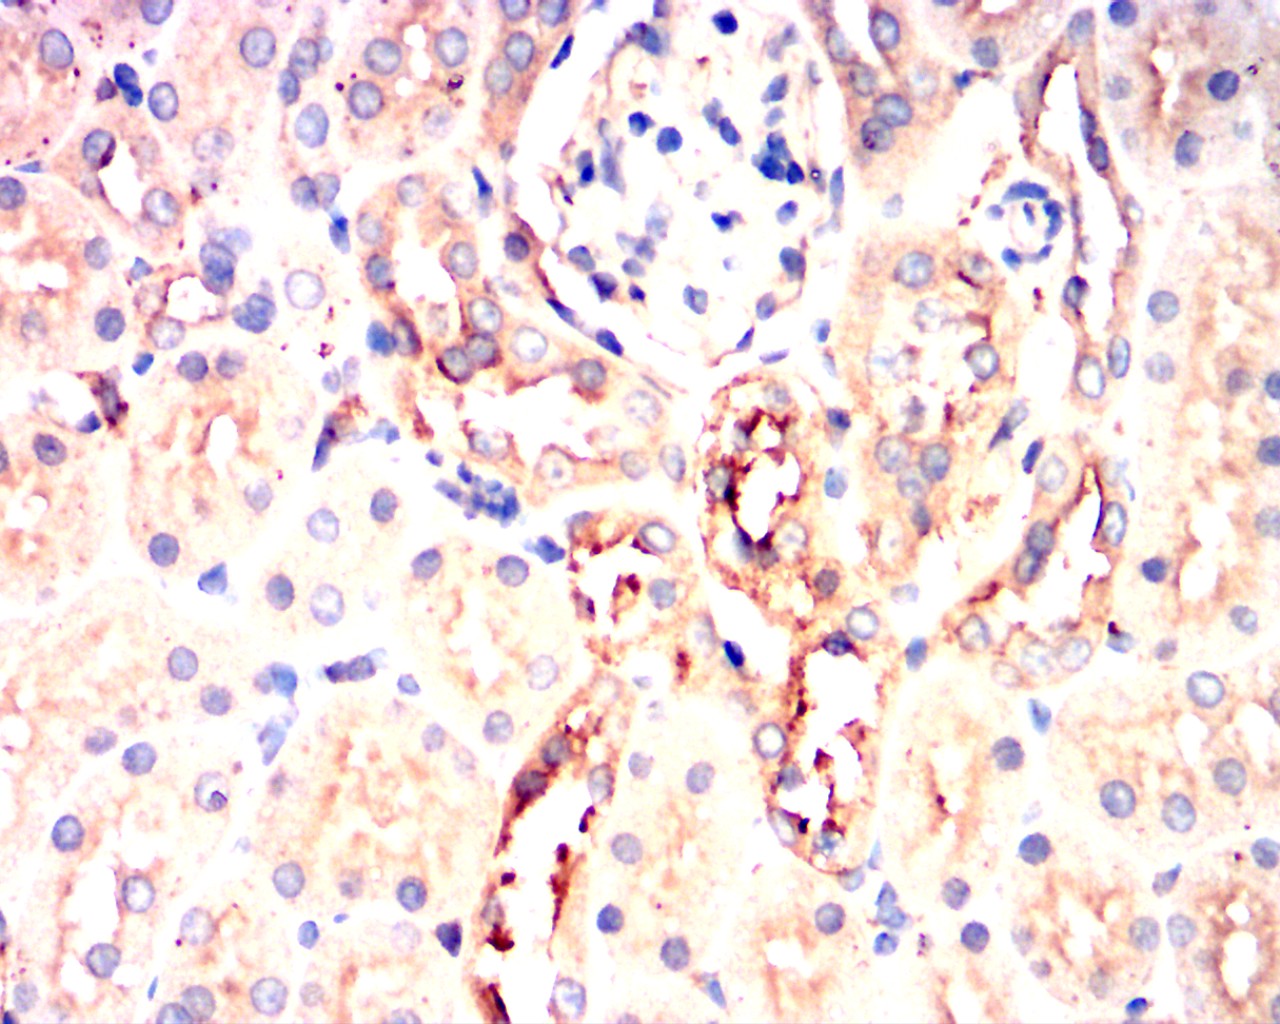

Immunohistochemical analysis of paraffin-embedded rabbit kidney showing cytoplasmic localization using PIK3CA mouse mAb with DAB staining.